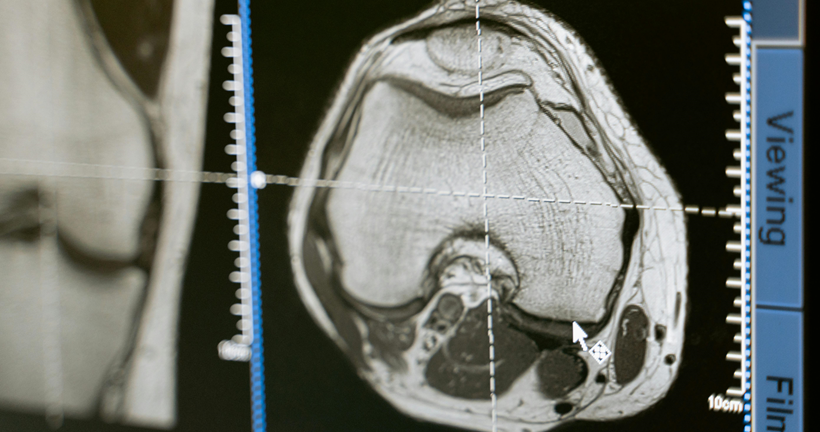

La presentación sintomatológica de la disfunción frontal dependerá de si la afectación predominante inmiscuye a regiones del cíngulo u orbitales. Además, las afectaciones de las funciones ejecutivas dependerán del daño en la corteza dorsolateral. Buscamos describir la relación existente entre la atrofia cerebral identificada en estudios de resonancia magnética estructural, PET-FDG y su implicación cognitiva sobre los pacientes con DFTvnf.

Como resultados en relación con los estudios analizados, se encontró que solo el 15% de artículos mantienen una correlación de áreas anatómicas - cognitivas, además se encontraron alteraciones en los dominios de atención, memoria y funciones ejecutivas mientras que los hallazgos de atrofia cerebral se localizan en áreas frontales, el cíngulo e ínsula.